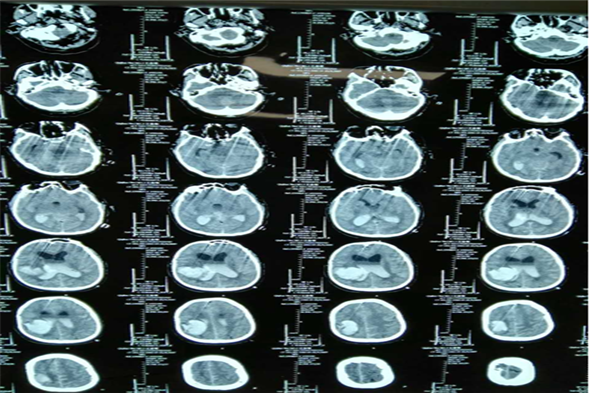

病例三 王某,男,66岁,脑出血、脑疝。

术前脑CT片

术后第三天脑CT

术后一周脑CT